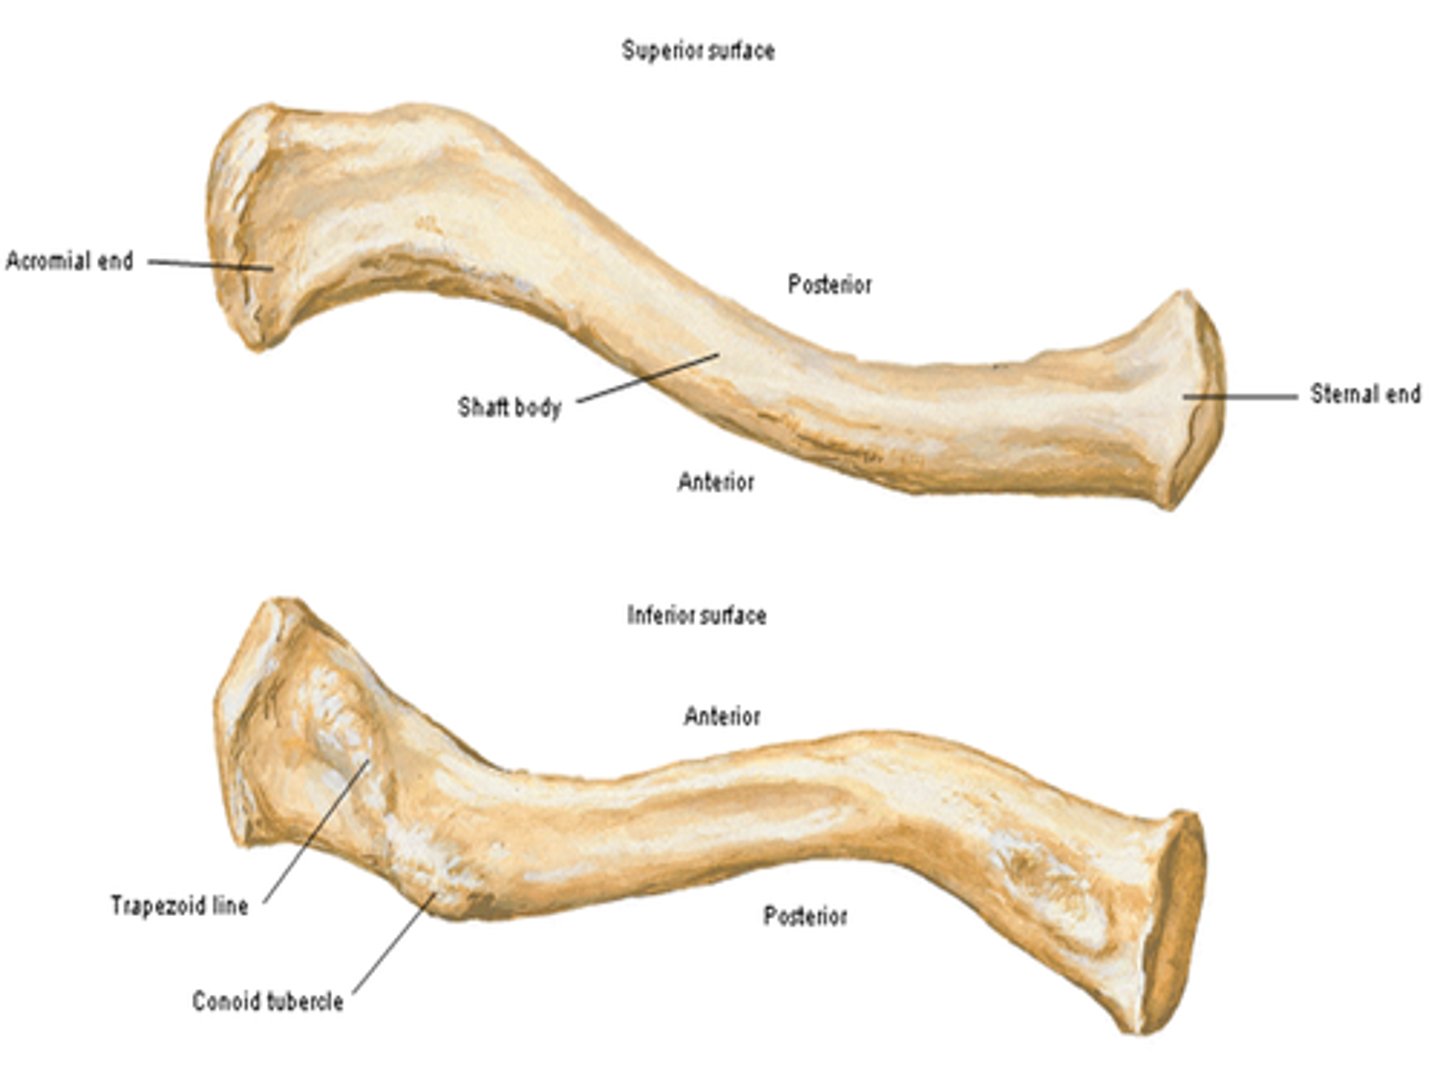

Parts of the clavicle:

- shaft

- superior surface

- inferior surface

Shaft of the clavicle:

double curved in the horizontal plane, which increases resilience

Middle half of the shaft of the clavicle:

convex anteriorly, and lateral half concave anteriorly

Sternal end of the shaft of the clavicle articulates:

articulates with manubrium via the sternoclavicular joint

Acromial end of the shaft of the clavicle articulates:

articulates with acromion via acromioclavicular joint

Location of superior surface of the clavicle:

lies deep to the platysma muscle and skin and it is smooth

Inferior surface of the clavicle:

rough surface with ligaments binding to it

Location of conoid tubercle of the inferior surface of the clavicle:

near acromial end of clavicle

Function of conoid tubercle on the inferior surface of the clavicle:

support for the medial part of the coracoclavicular ligament

Location of the trapezoid line of the inferior surface of the clavicle:

nearer to the acromial end than the conoid tubercle

Function of the trapezoid line of the inferior surface of the clavicle:

support for the lateral part of the coracoclavicular joint